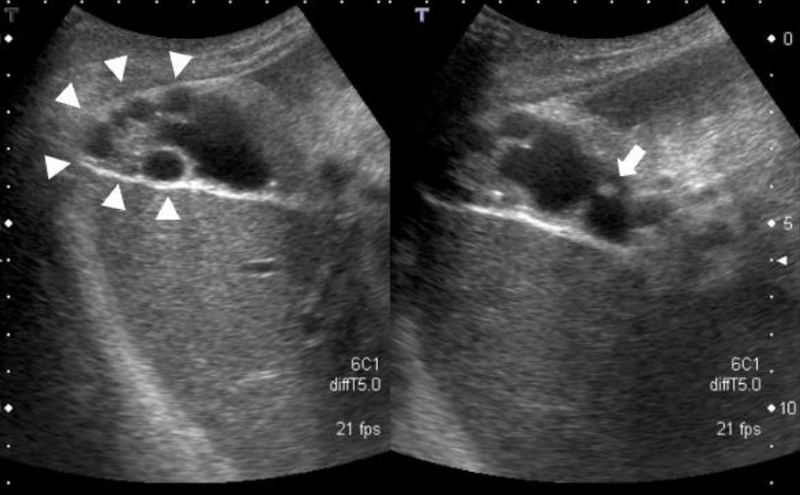

U cơ tuyến túi mật là một dạng tổn thương lành tính với biểu hiện đặc trưng là sự phì đại biểu mô, niêm mạc và cơ trơn. Lúc này, thành túi mật dày lên đôi khi hơn 10mm, có chứa túi thừa hoặc túi thừa giả (xoang Rokitansky-Aschoff) xâm lấn rất sâu, liên quan trực tiếp đến hiện tượng thành túi mật dày lên, đôi khi có thể lan ra ngoài lớp cơ.

Do u cơ tuyến túi mật không gây triệu chứng cụ thể nên chẩn đoán hình ảnh giữ vai trò rất quan trọng trong việc phân biệt chính xác tình trạng này với các tổn thương liên quan như ung thư túi mật, polyp túi mật, u tuyến, viêm túi mật cấp tính, viêm túi mật mạn tính, u hạt vàng, suy tim, giảm protein máu, viêm tụy cấp, viêm quanh gan,… Các phương pháp chẩn đoán được áp dụng phổ biến bao gồm: Chụp X-quang, siêu âm nội soi, chụp CT, chụp cộng hưởng từ (MRI).